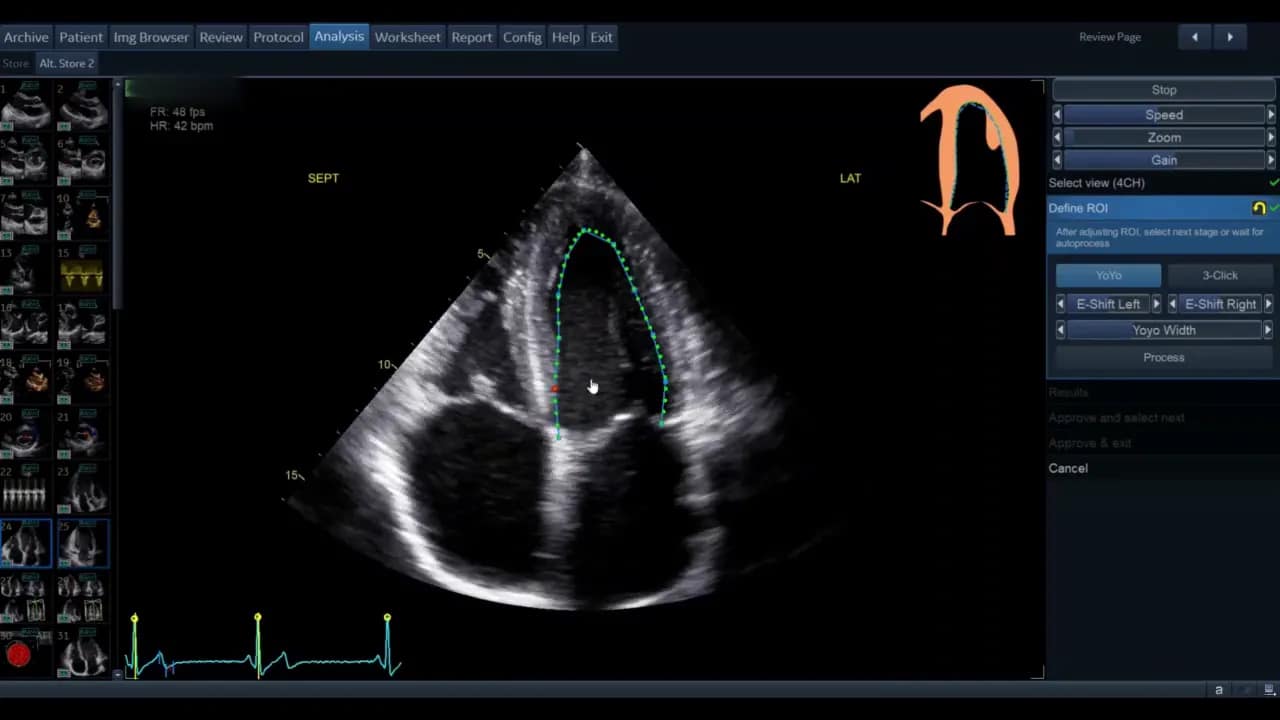

Schritt 3: Region of Interest (ROI) definieren

Sobald die Ansicht gewählt ist, gelangen Sie in die Phase der ROI‑Definition. Hier legt die Software die initiale Kontur für die automatische Wandsegmentverfolgung fest.

Die Standardkontur wird als grüne Linie (modellabhängig) angezeigt. Bewegen Sie den Cursor über diese Linie; rote Kreise erscheinen als Griffpunkte, die Sie anklicken, verschieben und loslassen können. Ziel ist eine möglichst genaue Platzierung entlang des inneren Myokardrandes ohne Papillarmuskeln und Trabekel zu ignorieren, soweit die Software dies zulässt.

- Wenn die vorgegebene Kontur passend ist, genügt das geringe Feintuning.

- Wenn die Kontur unbrauchbar erscheint, nutzen Sie die Drei‑Punkt‑Option. Dabei markieren Sie basal‑septal, basal‑lateral und den Apex manuell. Die Software interpoliert zwischen den Punkten.

Nach der manuellen Markierung können Sie die so erzeugte grüne Kontur wiederum per Griffpunkte feinjustieren. Ziel ist, dass die Kontur den endokardialen Rand im gesamten Zyklus plausibel abdeckt.